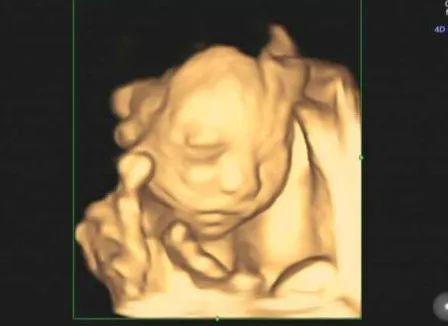

定是孕中期四维彩超检查

四维彩超能够表面成像,若胎儿有唇腭裂

四肢发育畸形等先天畸形

都能更清晰地查出来

也有利于医生做出判断

虽说四维彩超是能清晰呈现宝宝的轮廓

但并不代表宝宝的长相

1.四维呈现,立体写真

为胎儿拍摄写真和动态录像,准爸妈们清晰可见胎宝情况,让准爸妈可以和胎宝进行第次“视频会面”。

四维彩超能全方位、多角度地观察宝宝在子宫里的生长发育状况,为早期诊断胎儿先天性体表畸形等提供准确的临床参考依据。